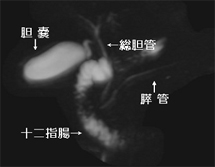

MRIは磁気共鳴画像とも呼ばれ、強い磁石と電波を使って、身体のあらゆる部位を撮影できる装置です。放射線を使用しないので被ばくの心配はなく、ラジオ波と同じ電波を利用して撮影しているため人体に優しい検査法です。 X線の画像と比べて筋肉・脊髄・内臓などが、明瞭かつ詳細に描出されます。MRIが有用なのは、脳梗塞・脳腫瘍などの脳疾患、動脈瘤などの血管障害、がん・子宮筋腫・椎間板ヘルニア・靭帯断裂など動きの小さい柔らかい組織での病変描出に適しています。 MRIの特性を利用して、造影剤を使わずに脳血管像(MRA) 胆管・膵管像(MRCP)の描出も可能です 。

| 脳血管像(MRA) | 胆管・膵管の検査(MRCP) | |